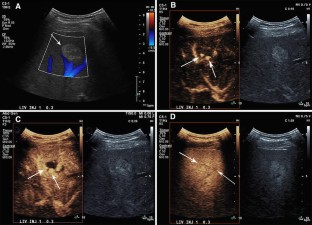

Fig. 3